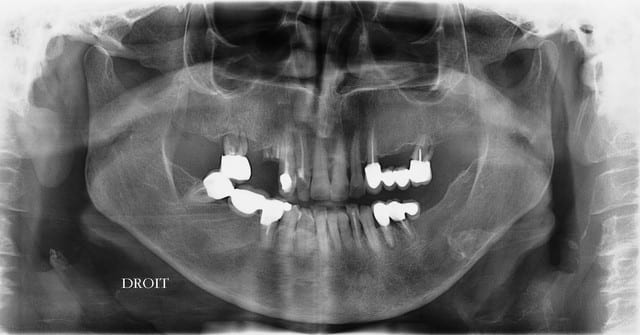

j'ai réalisé en juin 2008 ma seule pose d'implant chez une patiente sous biphosphonate. Cette patiente était sous BP depuis 4 ans; elle avait une très belle parodontite terminale avec abcès aigu qui a rendu l'extraction de sa 27 indispensable, et son médecin lui prescrivait ses BP sans lui avoir recommandé de faire une consult' chez son dentiste qu'elle n'avait pas revu depuis 10 ans.

l'avulsion a donc été faite, et la cicatrisation s'est produite assez lentement mais correctement;

la patiente ne voulait pas passer de la PAP maxillaire à la PAT.

comme elle ne ne disposait pas des moyens financiers nécessaires et que la cicatrisation s'était bien passée, je lui ai proposé un PDT avec 3 implants, barre d'ancrage, PAP et conservation d'une dent (en attendant le prochain implant);

L'AFSAPS considérant que la prise de BP par voie orale depuis plus de 3 ans ne contre-indique pas la pose d'implant,

la pose a été faite en flapless, la barre d'ancrage a été posée en 09/2008;

voici les photos avant de la pose de la barre en 09/2008 et la pano en 01/2009; RAS depuis